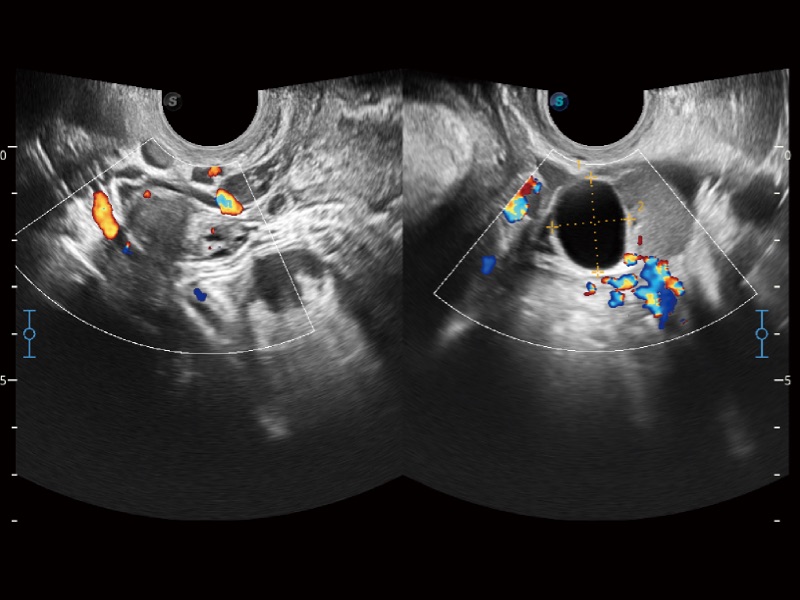

• SR Flow 高分辨率血流成像技术

高分辨率血流成像技术提高了对低速血流信号的检测能力。在提高空间分辨率的同时,也克服了血流外溢现象,为用户提供更加真实的血流动力学信息。

临床图